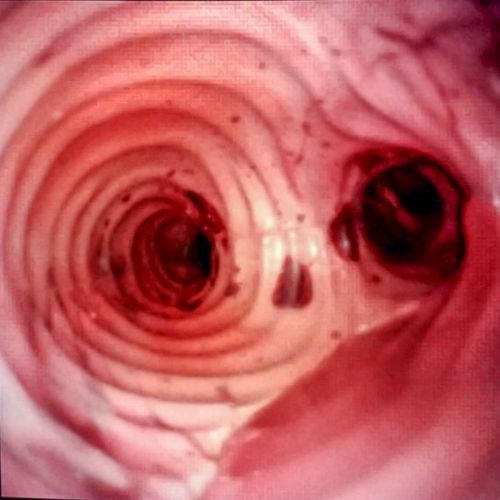

Boston Scientific had a kidney, ureter, and bladder model that was the gold standard at urology conferences, everyone was using it. It was realistic on the inside for realistic scope views. As it was created for scientific research it was not elegantly finished on the outside and the materials were sticky and unattractive. Boston Scientific wanted more. Their objective was a durable model that gave clinicians a realistic surgical experience both visually and tactilely. They wanted to be able to add and remove large kidney stones from the kidneys. They wanted the model to look great from the outside as well as the inside. And they needed a way to hold the organs in place during use. Also, a great addition would be a model designed to engage urologists in challenging ureteroscope navigation into the ureters on one side and have an easier and faster option to directly insert the scope in the ureter without having to steer through a difficult path on the other side.

Pulse MDM thought, wouldn’t it be cool to have a kidney that was clear from the outside so you could see the calyces but believably realistic from the inside scope view. Pulse MDM developed a kidney to do both. The clarity was so good we had to include a kidney cover so the urologist could not “cheat” by seeing the light of the ureteroscope from the outside when doing their navigation practice.

Boston Scientific wanted to give surgeons clinically relevant experience with their urology devices anywhere in the world. They asked Pulse MDM to develop Kidneys, Ureters, and a Bladder that were as real in look (through their visualization) and feel (using their urology devices) as possible. We included a custom shipping case with a custom foam insert to contain all the devices required for training. The models are portable so that there would never be any hesitation to offer surgeons hands-on practice with their whole category of devices and treatments in the urology space, including PCNL, lithotripsy, and ureteroscopy, anywhere in the world. The model was designed with modular components that can be swapped out to accommodate differing pathologies and new clinical scenarios, kidneys were created for easy stone introduction and replacement, and the interior view is painted to look just like the screenshots they provided our team from live patients. Our client said the model facilitates deeper clinical conversations with the surgeons as now they can offer repeat hands-on practice with common and uncommon surgical scenarios.